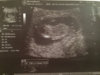

Jednak cos jest na zeczy:-)Dziewczynek![]()

Ja też bym chciała dziewczynkę... No ale wiadomo jak będzie drugi chłopak to też będę się cieszyć